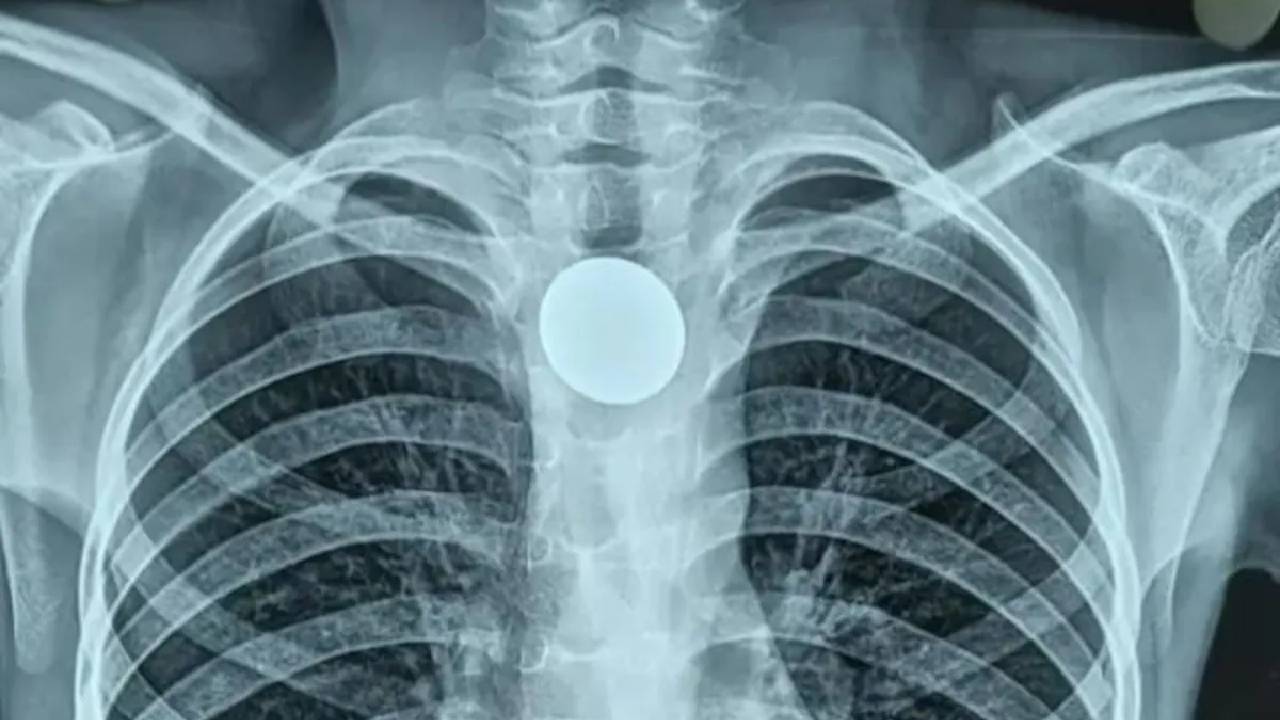

Coin Stuck In Throat: 12 ఏళ్ల బాలుడి గొంతులో ఇరుక్కున్న నాణేన్ని ఏడేళ్ల తర్వాత తొలగించిన అరుదైన ఘటన ఉత్తర్ ప్రదేశ్‌లో జరిగింది. హర్డోయ్ జిల్లా ఆస్పత్రిలో ఈఎన్‌టీ సర్జన్ డాక్టర్ వివేక్ సింగ్ మరియు అతని బృందం ఈ శస్త్రచికిత్సను నిర్వహించింది. సంక్లిష్టమైన శస్త్రచికిత్స నిర్వహించిన వైద్యలు బృందం విజయవంతంగా నాణేన్ని తొలగించింది. ఏళ్ల తరబడి అనుభవిస్తున్న నొప్పి, వేదన నుంచి బాలుడు విముక్తి పొందాడు.

రాష్ట్రంలోని బఘౌలీలోని మురళీపూర్వ గ్రామానికి చెందిన అంకుల్ అనే బాలుడికి ఏప్రిల్‌లో కడుపునొప్పి రావడంతో కష్టాలు మొదలయ్యాయి. ప్రైవేట్ వైద్యుడి వద్ద చికిత్స తీసుకున్న తర్వాత కోలుకున్నప్పటికీ, జూన్ 4న అతను గొంతు నొప్పిగా ఉందని చెప్పడంతో అతని తాత అతడిని జిల్లా ఆస్పత్రికి తీసుకెళ్లాడు. వైద్యులు పరీక్షించిన తర్వాత బాలుడి గొంతులో రూపాయి నాణేం ఇరుక్కుని ఉందని చెప్పారు. టెలిస్కోప్ పద్దతిని ఉపయోగించి సర్జరీ చేసిన వైద్యులు నాణేన్ని తొలగించారు.

ఏడేళ్ల పాటు బాలుడి గొంతులోనే నాణేం ఇరుక్కుపోయి ఉందని, ఇలాంటివి చూడటం చాలా అరుదని, ఇది బాలుడి ఎదుగుదలను మాత్రమే కాకుండా అతని శారీరక ఎదుగుదలను కూడా ప్రభావితం చేసింది, పిల్లాడు 12 ఏళ్ల వయస్సున్న పిల్లాడిలా లేదని డాక్టర్ వివేక్ సింగ్ చెప్పారు. ఇలాంటి కేసుల్లో ఇన్ఫెక్షన్లు వచ్చే అవకాశం ఎక్కువ అని, తొలగించిన తర్వాత కూడా అబ్బాయికి సమస్యలు వచ్చే అవకాశం ఉందని చెప్పారు. దీంతో రెగ్యులర్ చెకప్‌కి రావాలని కుటుంబ సభ్యులకు సూచించినట్లు వెల్లడించారు.